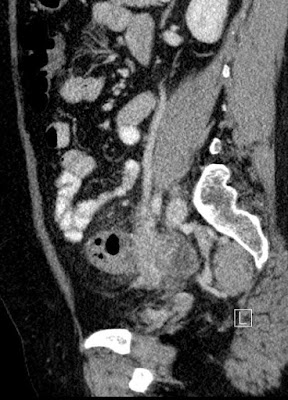

coronal reconstruction

ovarian vein pointing at the lesion

Tubular fluid-filled nonvascular structures in the pelvis that are associated with an adnexal mass are suggestive of dilated fallopian tubes that correlate with cases of pelvic inflammatory disease. A finding of an adjacent or surrounding complex mass confirms the diagnosis of TOA.